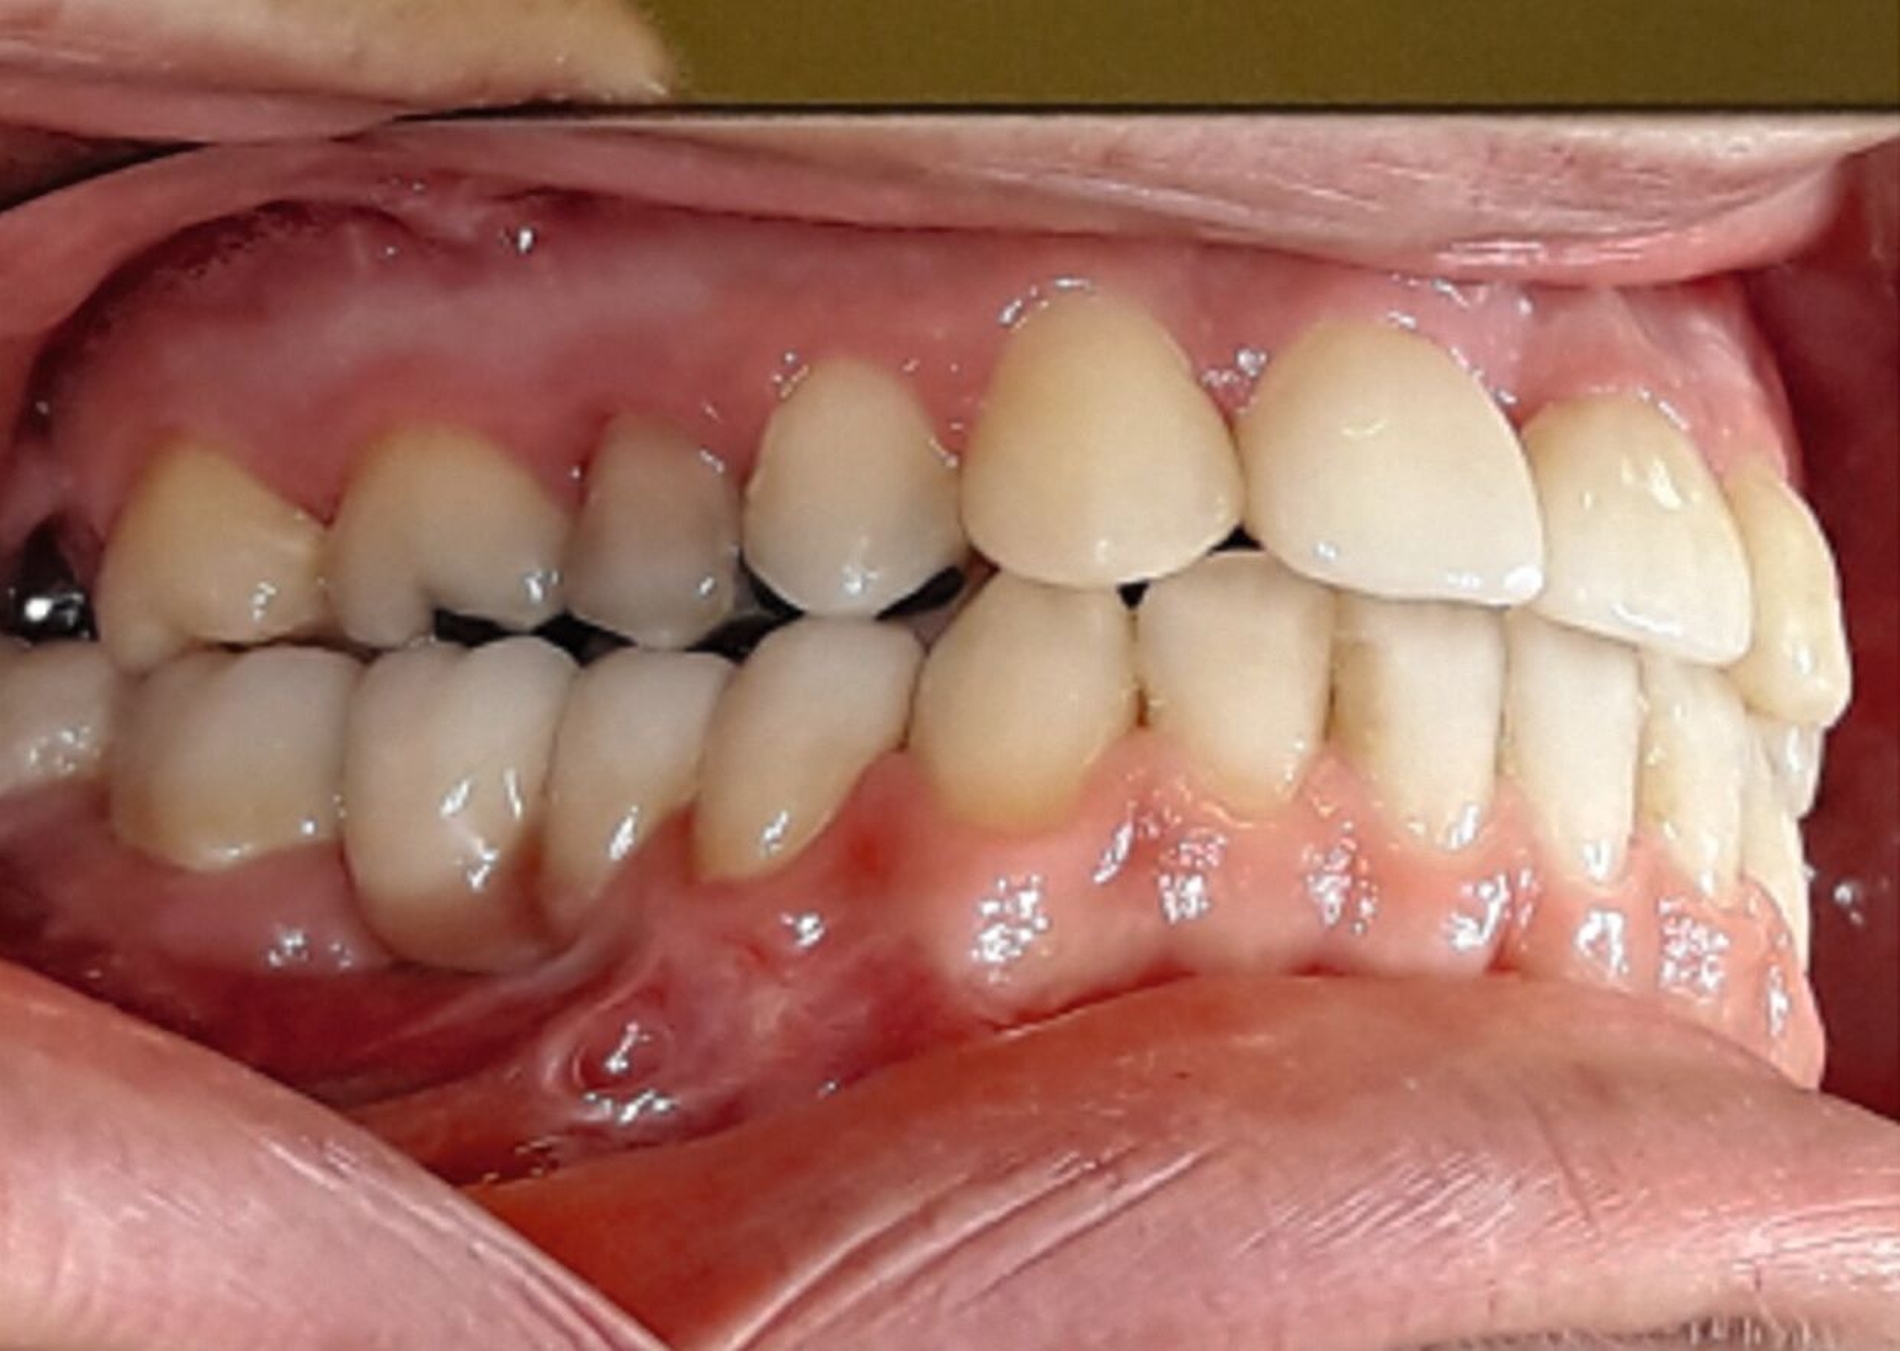

Ein 25-jähriger Patient stellte sich mit dem Wunsch nach Optimierung seines Erscheinungsbildes und seiner Kaufunktion in der kieferorthopädischen Praxis vor (Abbildung 1). Klinisch zeigten sich eine Angle-Klasse-III-Verzahnung mit einer 3/4 Prämolarenbreite Mesialokklusion beidseits und ein zirkulärer Kreuzbiss von 18–12/48–41 und 21–28/31–37. Es lagen ein negativer Overjet von -6,7 mm und ein Overbite von 5,1 mm vor. Eine Mittellinienverschiebung wurde sowohl im Oberkiefer – mit einer Abweichung von 4 mm nach rechts – als auch im Unterkiefer – mit einer Abweichung von 3 mm nach links – diagnostiziert (Abbildungen 2 und 3).